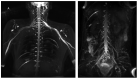

In the present study, through a case series, we highlighted the role of magnetic resonance (MR) in the identification and diagnosis of peripheral neuropathies. MR neurography allows the evaluation of the course of nerves through 2D and 3D STIR sequences with an isotropic voxel, whereas the relationship between nerves, vessels, osteo-ligamentous and muscular structures can be appraised with T1 sequences. Currently, DTI and tractography are mainly used for experimental purposes. MR neurography can be useful in detecting subtle nerve alterations, even before the onset of symptoms. However, despite being sensitive, MR neurography is not specific in detecting nerve injury and requires careful interpretation. For this reason, MR information should always be supported by instrumental clinical tests.